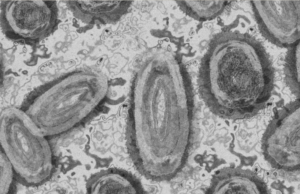

Viruela de mono: Qué es y cuáles son sus síntomas

A partir del 7 de mayo cuando se dio a conocer el primer caso de viruela de mono en el Reino Unido, las alarmas...